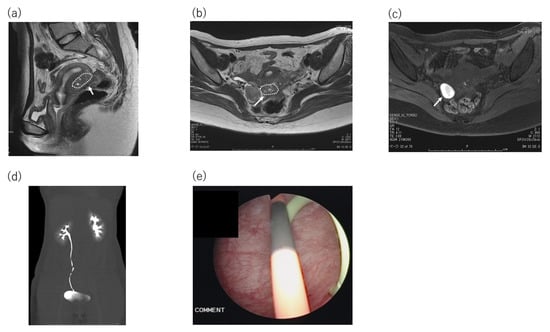

A Case of Elastography-Assisted Laparoscopic Fertility Preservation for Severe Deep Endometriosis Causing Ureteral Stenosis and Subtype II Adenomyosis

2. Case Presentation